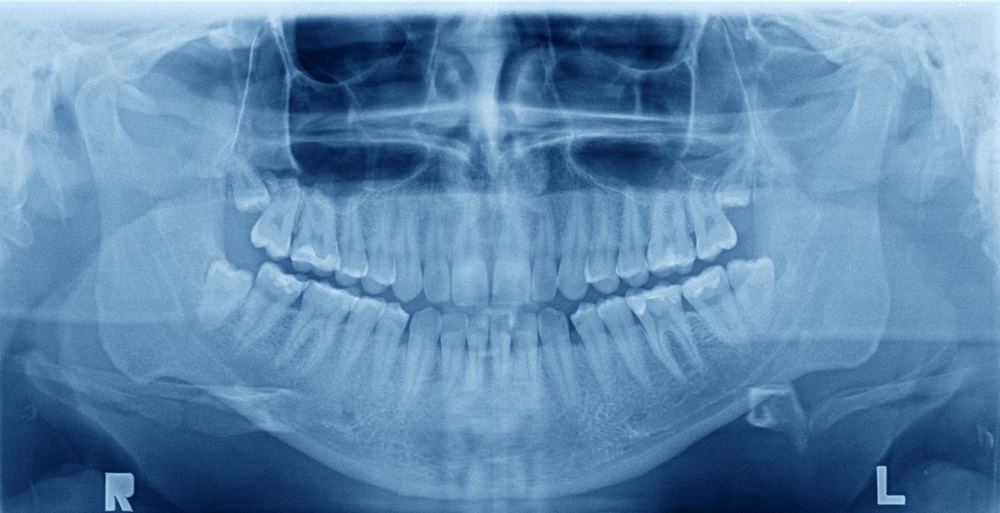

How Dental X-rays Improve Diagnosis And Treatment Planning

Finding out what's happening inside your mouth can feel like a mystery. Luckily, dental X-rays use advanced technology to reveal the hidden details of our oral health.  The Evolution of Dental X-rays The transformation from film to digital has revolutionized dental imaging, enhancing diagnosis and...  Read More

Advantages of 3D in radiology for patients and dentists

One of the greatest technological advances in recent times has been achieved in the area of radiology. Specifically, for a few years now, we have had scanners that allow 3D images to be made, so that diagnoses can be carried out much more precisely. Panoramic three-dimensional images When we talk...  Read More